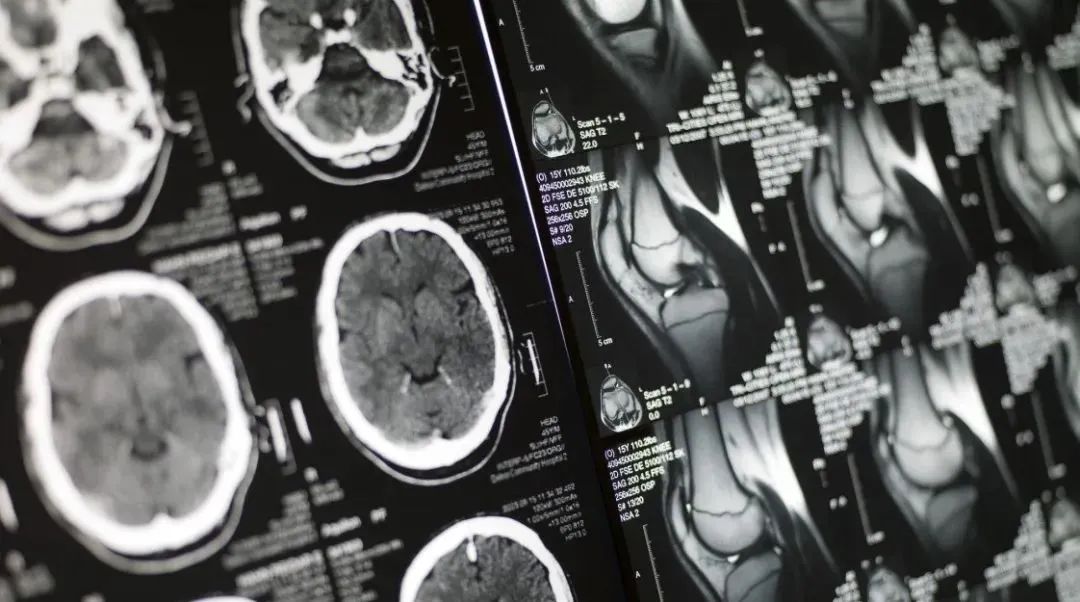

兩年前,新冠病毒在武漢暴發(fā)時,AI影像醫(yī)療曾留下輝煌戰(zhàn)績。 那時,AI影像起到重要作用的基礎(chǔ)是,針對最初的新冠病毒,患者的肺部影像數(shù)據(jù)可以作為診斷新冠肺炎患者的標(biāo)準(zhǔn)之一。 例如,業(yè)界首個針對新冠肺炎智能評估系統(tǒng)在4天內(nèi)研發(fā)上線,輔助醫(yī)生對患者肺部CT影像快速篩選高危和疑似病例、定量分析、療效評估方面發(fā)揮重要作用。據(jù)悉,AI醫(yī)療影像診斷系統(tǒng)能夠在5秒內(nèi)完成數(shù)百張影像的初步診斷,協(xié)助基層醫(yī)療機(jī)構(gòu)辨別感染者。

AI醫(yī)療影像在上海戰(zhàn)“疫”中缺席并非是技術(shù)上無法達(dá)到,而是病毒變異造成醫(yī)療應(yīng)用場景發(fā)生了變化。醫(yī)院科室雖有肺部AI影像這把利器,卻在變異毒株奧密克戎面前失去戰(zhàn)場。